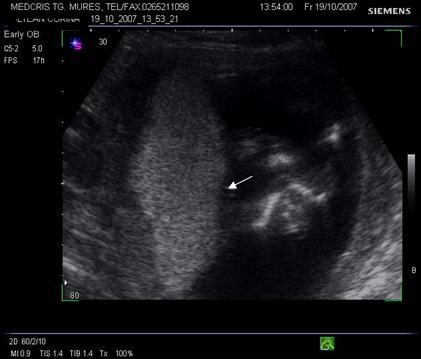

Fig. nr. 208. Placenta gr O la 16 saptamani gestationale, cu sageata se remarca insertia centrala placentara , a cordonului ombilical